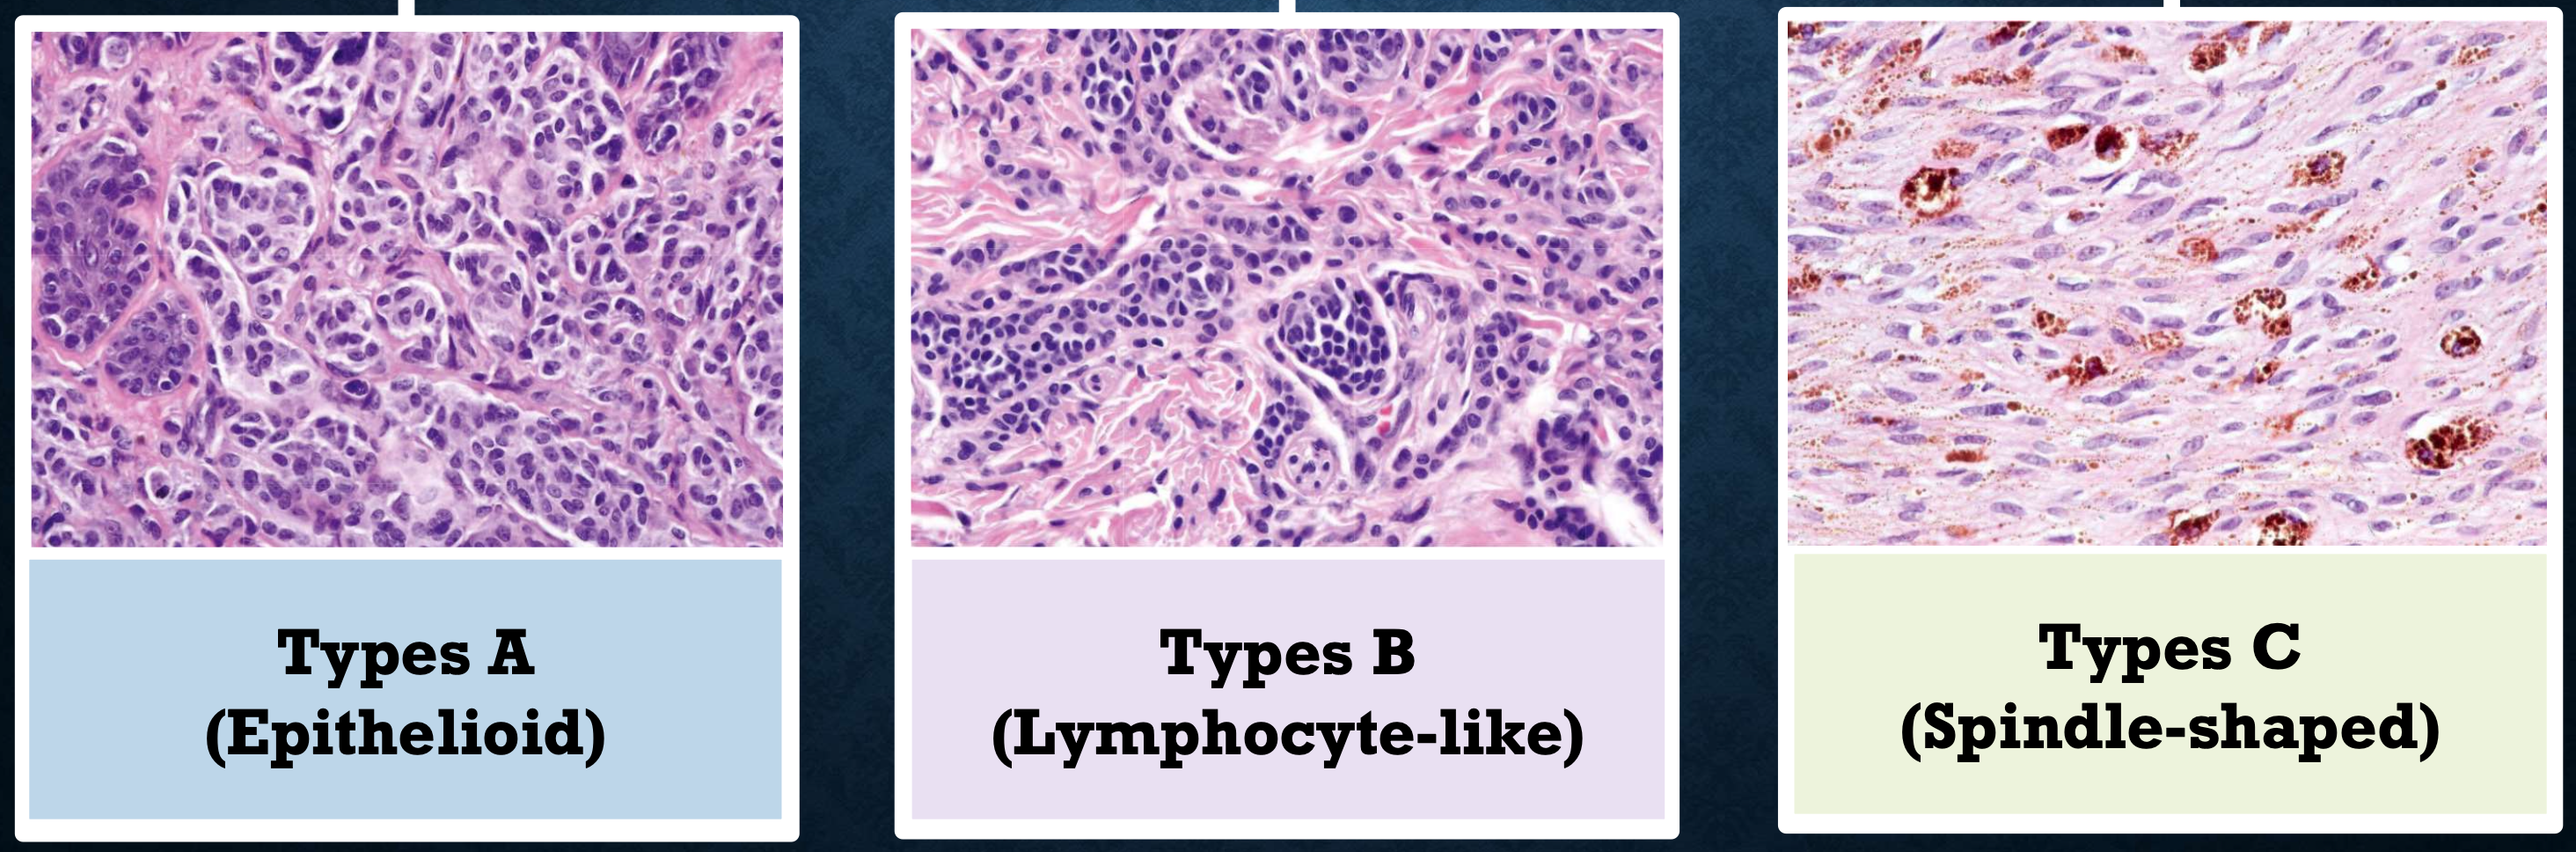

組織

- Cell 分三類:

- A: Epithelioid (在 epi)

- B: Lymphocyte-like

- Spindle-shaped